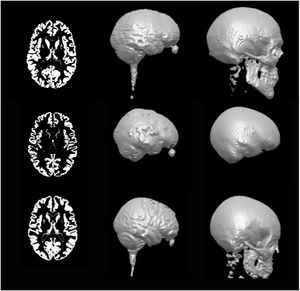

A Novel Procedure for Rapid Imaging of Adult Mouse Brains with MicroCT using Iodine-Based Contrast

Publication: PLoS One. 2015 Nov 16;10(11):e0142974. PMID: 26571123 | PDF Authors: Anderson R, Maga AM. Institution: Center for Developmental Biology and Regenerative Medicine, Seattle Children's Research Institute, Seattle, WA, USA. Background/Purpose: High-resolution Magnetic Resonance Imaging (MRI) has been the primary modality for obtaining 3D cross-sectional anatomical information in animals for soft tissue, particularly brain. However, costs associated with MRI can be considerably high for large phenotypic screens for gross differences in the structure of the brain due to pathology and/or experimental manipulations. MicroCT (mCT), especially benchtop mCT, is becoming a common laboratory equipment with throughput rates equal or faster than any form of high-resolution MRI at lower costs. Here we explore adapting previously developed contrast based mCT to image adult mouse brains in-situ. We show that 2% weight per volume (w/v) iodine-potassium iodide solution can be successfully used to image adult mouse brains within 48 hours post-mortem when a structural support matrix is used. We demonstrate that hydrogel can be effectively used as a perfusant, which limits the tissue shrinkage due to iodine. Funding:

A. A representative high-resolution MRI scan of an age matched C57BL/6J displaying the brain and the mCT overlay (yellow outline) from [21]. B. Equivalent cross sections from five females that constitute the Group A (Hg perfusion) after 48h of staining in 2% I2KI. C. One individual that constitutes Group B (PFA perfusion) after 48h of staining in 2% I2KI. D-F: Heatmaps showing the difference in the obtained segmentations with respect to the reference MRI atlas constructed from [21,22]. To remove volumetric differences due to sex and age, we isometrically scaled our segmented brains to match the volume of the reference MRI atlas. Root mean square (RMS) errors are calculated after the scaling. D: Comparison of our Group A mCT atlas. RMS = 0.128 mm. E: Comparison of individuals of Group A. RMS values are 0.172 mm, 0.143 mm, 0.156 mm, 0.142 mm, 0.196 mm respectively. F: Comparison of Group B. RMS = 0.232 mm. All comparisons are rendered on MRI reference atlas. Grey area in the heat map indicate regions of large difference (>0.5 mm) either due to extreme shrinkage or difference in segmentation. Using this outline as the boundary, stained brains were interactively segmented using the editor module of 3D Slicer. |